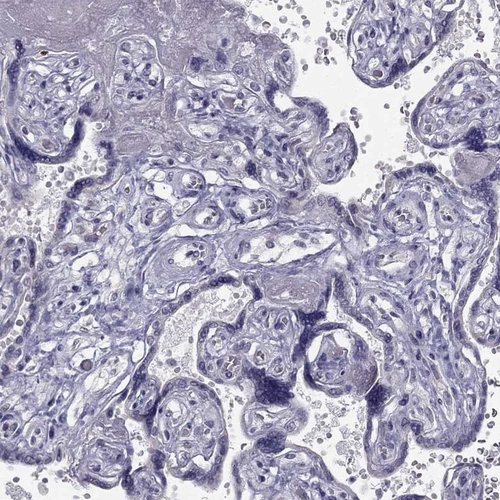

Immunohistochemistry analysis in human fallopian tube and placenta tissues using Anti-C5orf49 antibody. Corresponding C5orf49 RNA-seq data are presented for the same tissues.